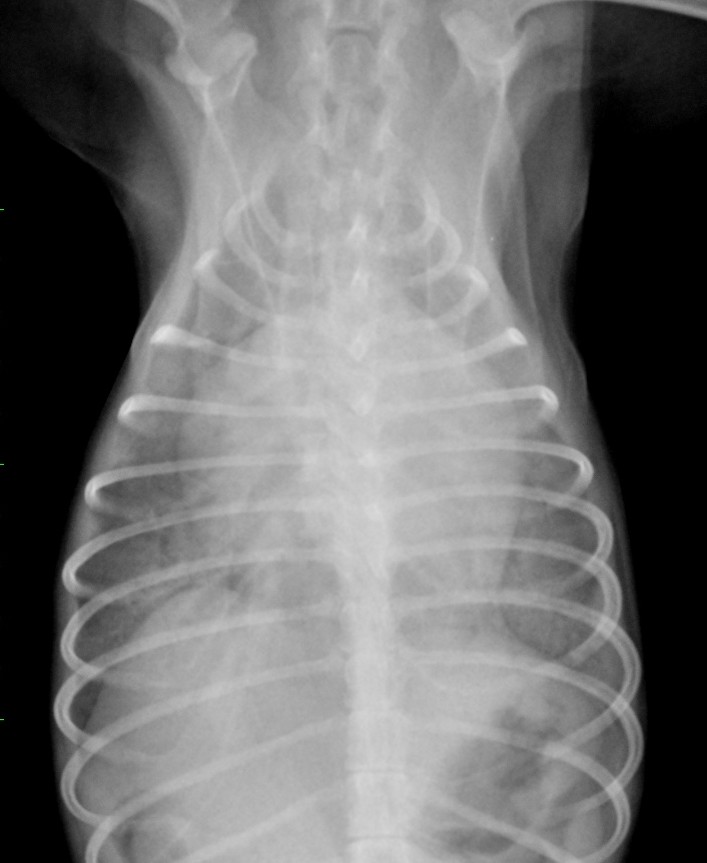

僧帽弁閉鎖不全症 ~症状~

ワンちゃんの心臓病で一番多い病気 それが 僧帽弁閉鎖不全症 同じ意味で弁膜症、僧帽弁逆流、僧帽弁粘液腫様変性な…